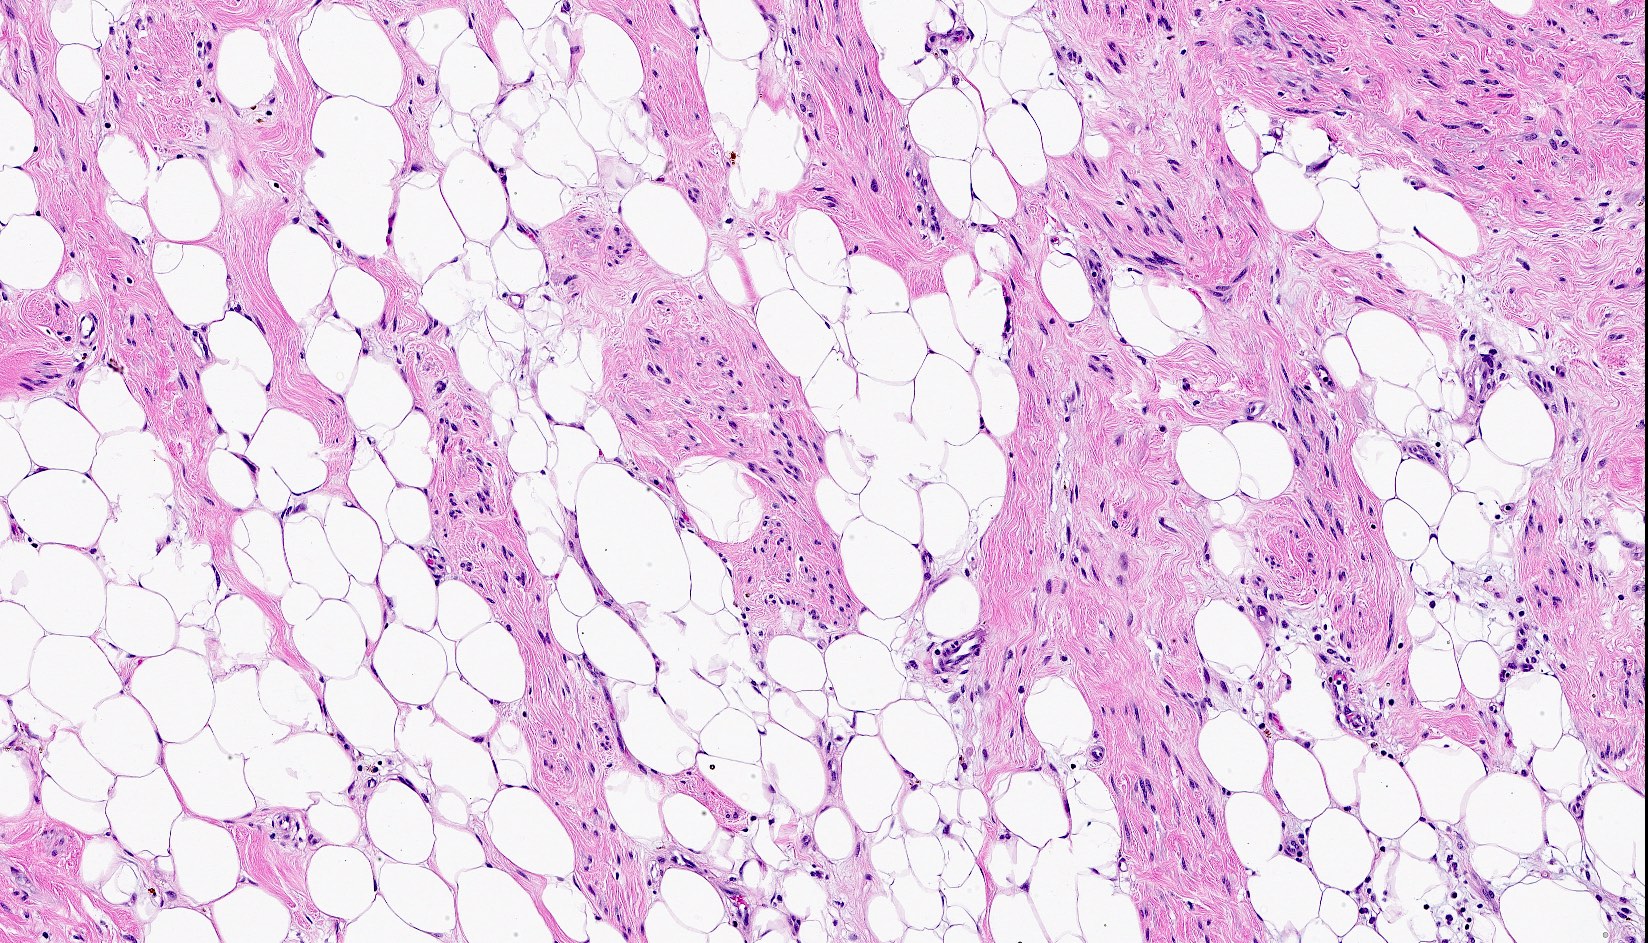

Microscopic (histologic) images

- Bland, uniform, short to elongated spindle cells arranged as short haphazard intersecting fascicles admixed with bands of hyalinized, brightly eosinophilic collagen and variable amounts of fat

- No more than mild nuclear atypia

- Mitoses usually absent, atypical mitoses and necrosis absent

- Mast cells common, perivascular lymphocytic infiltrates on occasion

- Lipomatous: abundant adipocytic component